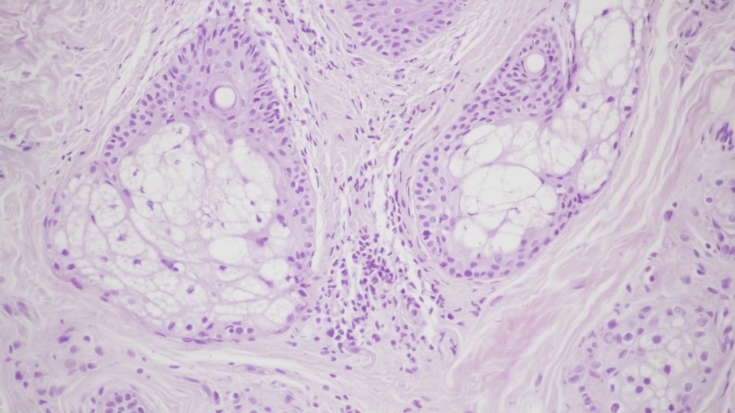

При контрольній гістологічній підготовці ділянки шкіри перед проведенням лікувальних заходів відзначалася вогнищева значно виражена запальна інфільтрація в дермі у вигляді вогнищевих скупчень лімфоцитів і гістіоцитів. (мал. 1а, b). Проліферація дрібних судин капілярного і синусоїдного типу супроводжувалася периваскулярною лімфоїдно-клітинною інфільтрацією (мал. 1c). Навколо окремих волосяних фолікулів і сальних залоз запальна інфільтрація стимулювала проліферацію фібробластів і розвиток склеротичних процесів. (мал. 1d).

Мал. 1. Морфологічна картина шкіри перед лікувальними заходами: вогнищева запальна інфільтрація дерми, х200; запальна інфільтрація навколо волосяних фолікулів, ознаки фіброзу, х200; проліферація дрібних судин капілярного типу з периваскулярної лімфоїдно-клітинною інфільтрацією, х200; сальні залози з вогнищевою запальною інфільтрацією в прилягаючій дермі, х200.